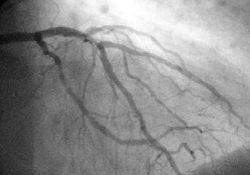

Angiogram of the coronary arteries.

In difficult cases or in situations where intervention to restore blood flow is appropriate, coronary angiography can be performed. A catheter is inserted into an artery (usually the femoral artery) and pushed to the vessels supplying the heart. A radio-opaque dye is administered through the catheter and a sequence of x-rays (fluoroscopy) is performed. Obstructed or narrowed arteries can be identified, and angioplasty applied as a therapeutic measure (see below). Angioplasty requires extensive skill, especially in emergency settings. It is performed by a physician trained in interventional cardiology.